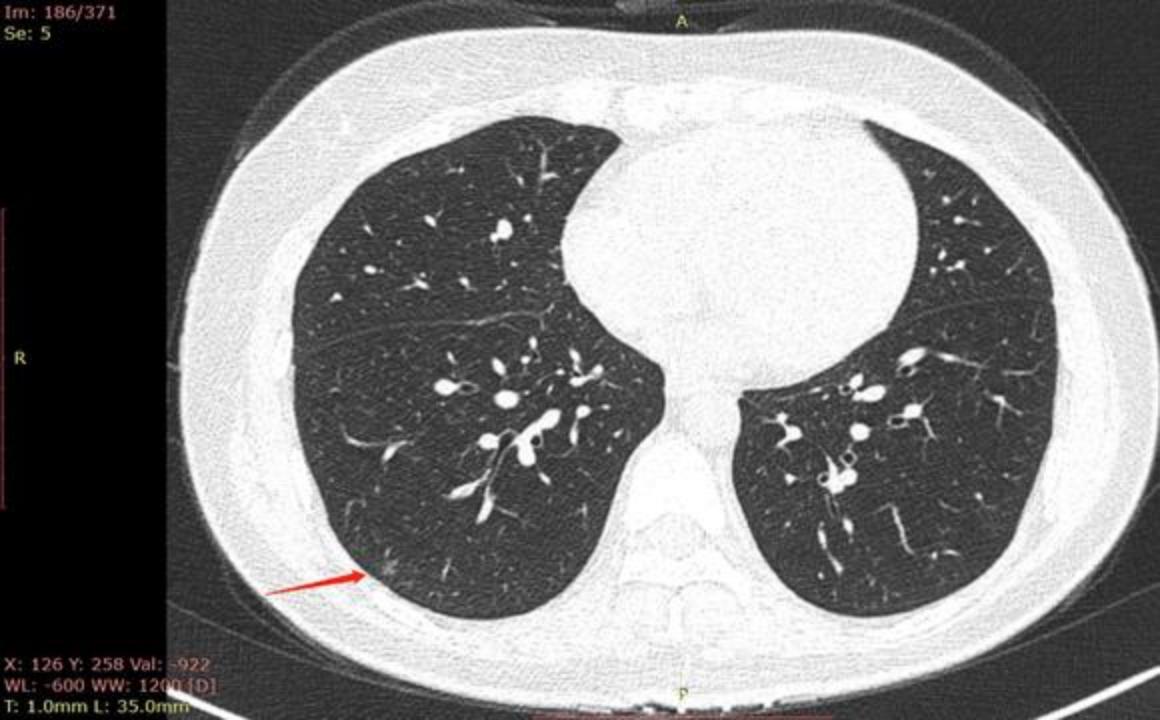

二、2022年4月13日第一次复查XH医院拍了CT,医生说不太好,恶性风险高,需要手术;去肿瘤医院问了一个医生说,比较小,也没有明显的恶性特征,3个月后再拍CT复查。

CT截图:

三、2022月7月14日第二次肿瘤医院复查拍CT,结果如下:

看了医生,医生说比较小,也没有明显的恶性特征,比较特殊,不是实性也不是磨玻璃的,中间可能是空气,一个空腔,可能就是介质,3-6个月后随访